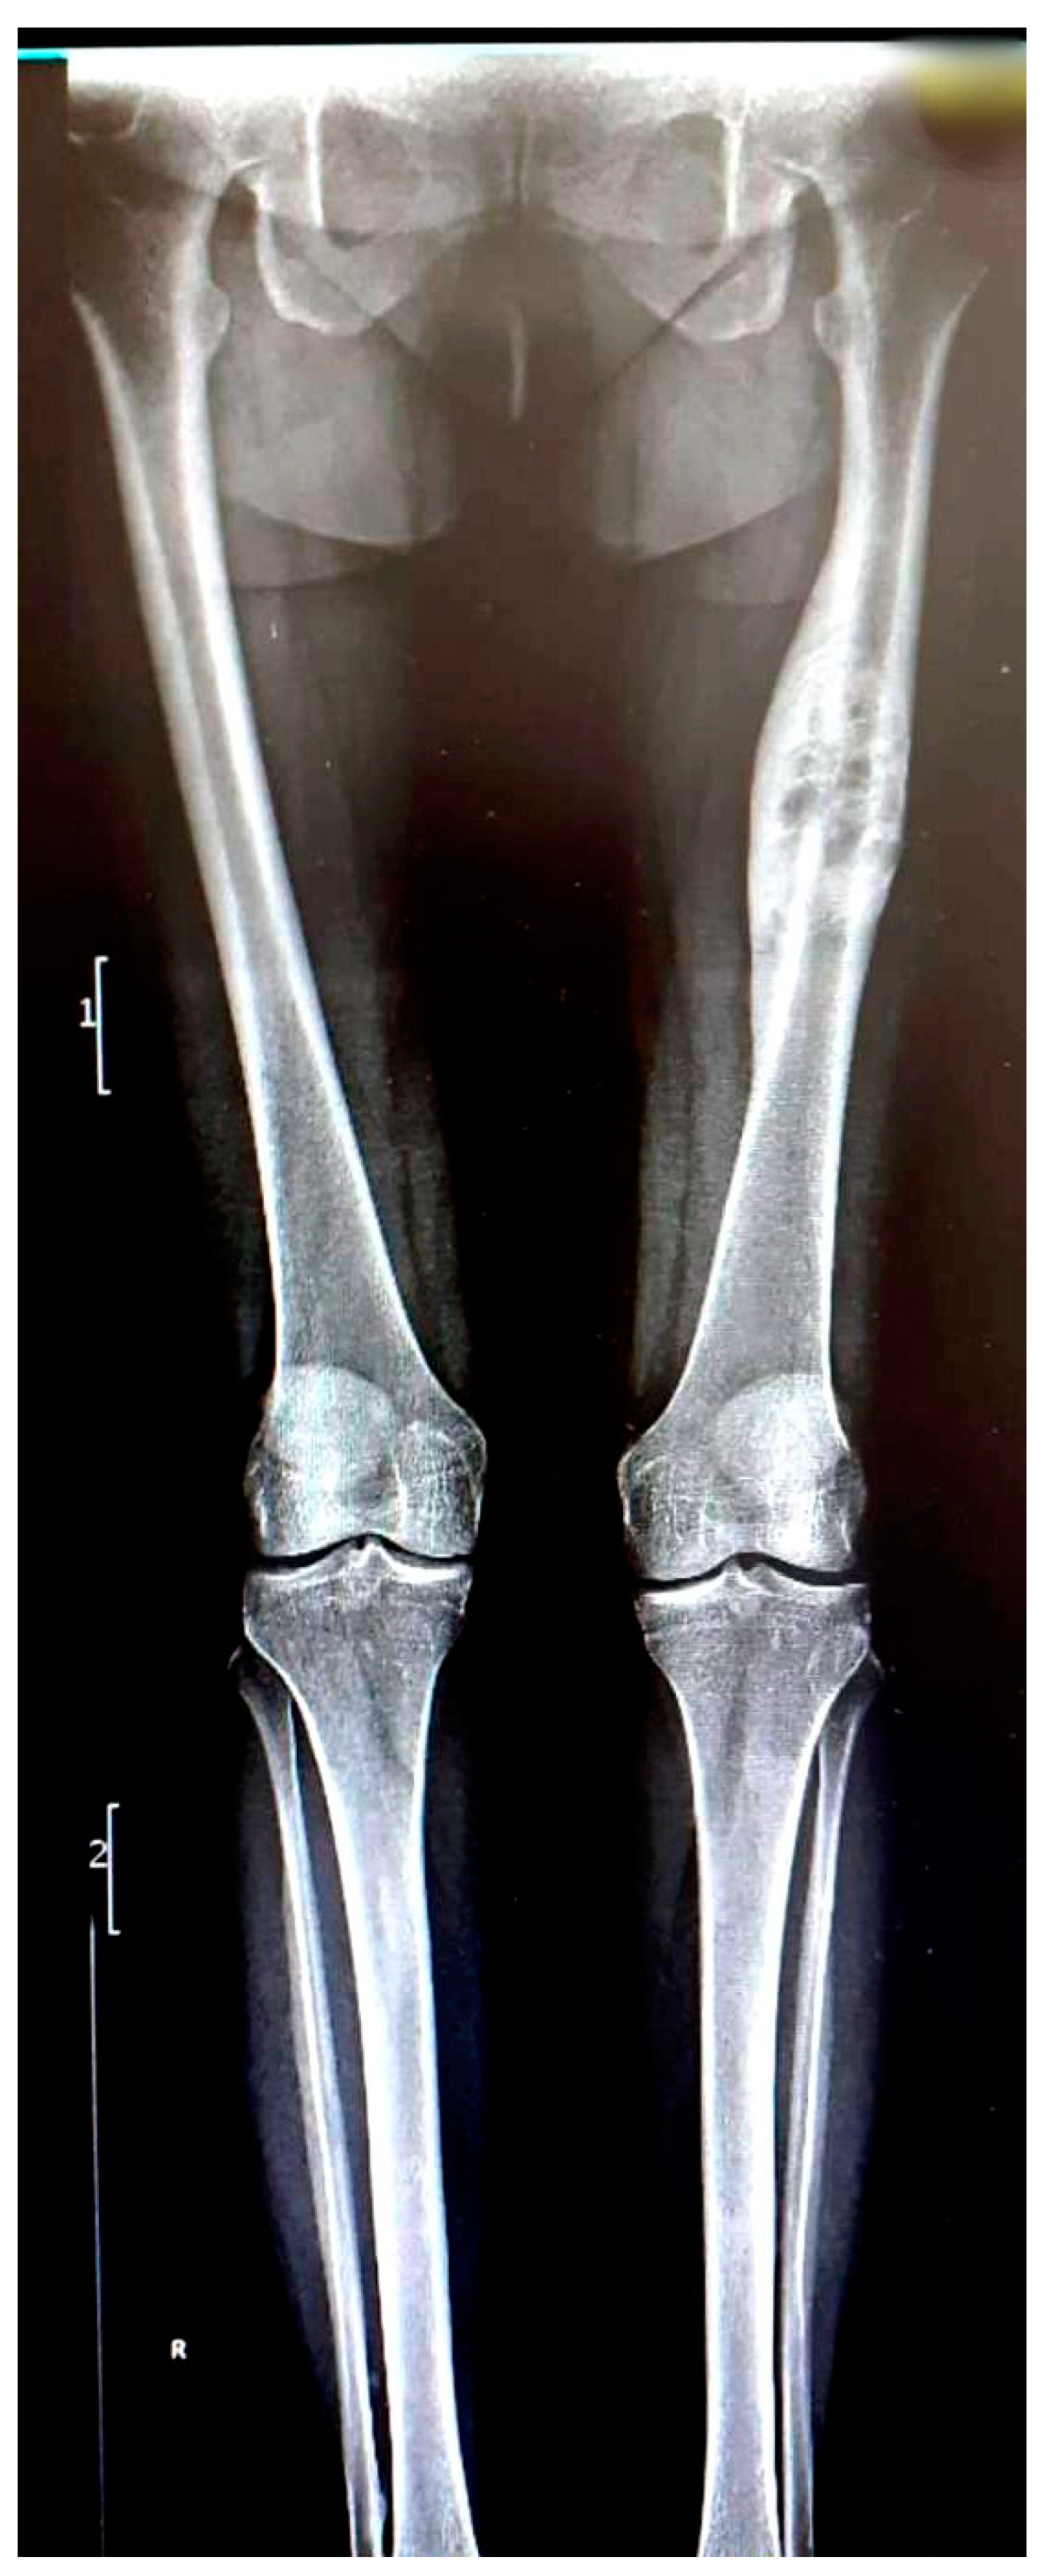

We present the case of a 46-year-old female patient who presented to the orthopedics and traumatology department of the University Emergency Hospital of Bucharest with severe pain in the left thigh and limitation of joint mobility. Following the clinical examination, the patient complained of pain in the middle third of the left thigh in the antero-medial part; the pain appeared spontaneously and was aggravated during physical activity. The pain started about two years ago, but the patient experienced complete pain relief after the administration of non-steroidal anti-inflammatory drugs. In the last six months, the patient presented an increase in pain intensity without significant improvement following the administration of non-steroidal anti-inflammatory drugs. The patient used non-steroidal anti-inflammatory drugs daily, without a significant improvement in pain, which significantly affected her quality of life. No shortening of the limbs or stiffness in the adjacent joints was observed. At the local examination, the patient had normal skin, without local changes, without inflammatory signs present, and no signs of ischemia. An X-ray of the femur in the antero-posterior and lateral incidence was performed which identified a unique bone lesion with dimensions of approximately 12/10 cm in the coronal plane located on the antero-medial cortex of the femur with a mixed appearance (Figure 1 and Figure 2). After that, we performed a whole-body scintigraphy which highlighted the same bone lesion described in the radiological examination with moderate uptake in the late phase, without highlighting other associated bone lesions.

Figure 1. Full-leg X-ray in the antero-posterior view showing a sclerotic bone lesion (12 cm) associated with lytic areas with thickening of the bone cortex.

Figure 2. Lateral view X-ray of the femur showing sclerotic bone associated with lytic areas with thickening of the bone cortex.